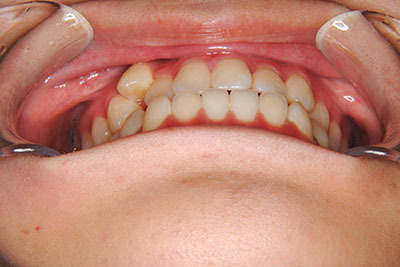

歯が乳歯から永久歯に生え変わった小学生高学年や、中高生でも矯正治療に手遅れということは全くありません。

成長中の顎の骨を矯正できたり、この時期の矯正はおとなになってから矯正治療を始めるよりも短期間で済むことがほとんどです。当院だとおおよそ1年で動的治療(マルチブラケット装置をつける期間)が終わることが多いです。